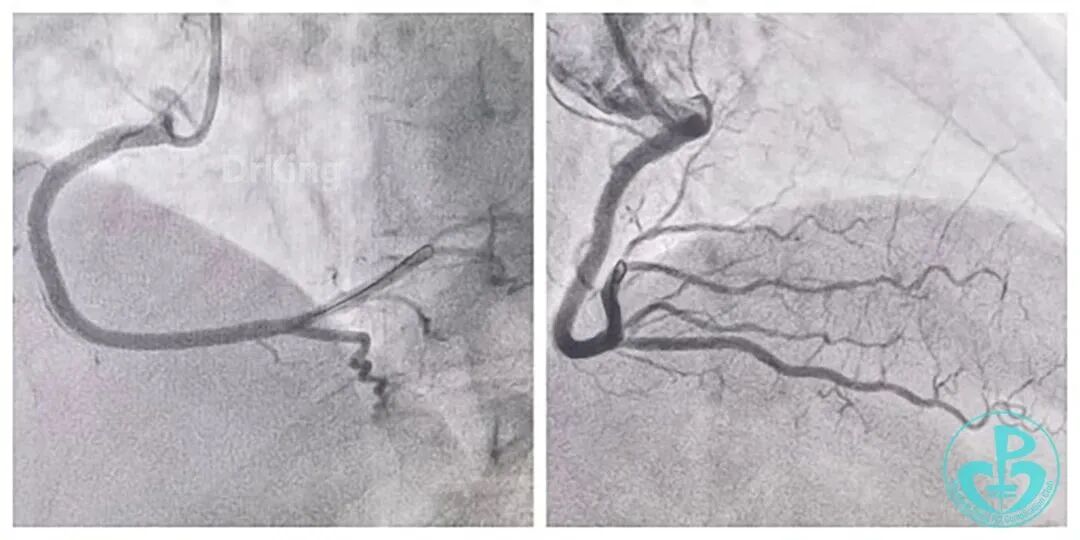

LAD开口完全闭塞,无(明确)残端,无同侧侧支供血,左侧仅剩较小的LCX及RI。RCA-PDA→S→m&dLAD侧支循环逆冠显影(RCA是心脏最主要的供血血管,相当于左主干;后文图有间隔支侧支显示)。

导丝推进顺利,KDL交换为单腔微导管,逆向造影指引导丝送至LAD中远段真腔内,交换工作导丝,全程仅用了9分钟,IVUS精准、优化指导下PSP,DES 1枚,结果理想。